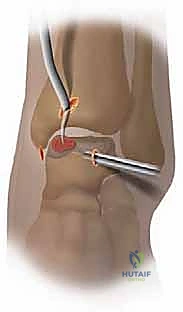

1. Portal Placement and Joint Access

We’ll start with our standard portals. Remember, precise placement and careful soft tissue dissection are key to avoiding neurovascular injury.

- Anteromedial Portal:

- Identify the tibialis anterior tendon and the medial malleolus.

- Make a small skin incision, approximately 1 cm, just medial to the tibialis anterior tendon at the level of the ankle joint line.

- Use a mosquito clamp to bluntly dissect down to the joint capsule. Feel for the capsule.

- Insert the blunt trocar and cannula into the joint. You should feel a distinct pop as you penetrate the capsule.

- Confirm intra-articular placement with saline inflow.

- Anterolateral Portal (Working Portal):

- With the arthroscope in the anteromedial portal, identify the lateral gutter and the extensor digitorum longus tendons.

- Transilluminate from the anteromedial portal to guide your placement.

- Make a 1 cm skin incision just lateral to the peroneus tertius tendon, again at the joint line.

- Bluntly dissect with a mosquito clamp. This is where the superficial peroneal nerve is most vulnerable.

- Insert the blunt trocar and cannula.

* FIG 5 • Standard anteromedial and anterolateral portals for ankle arthroscopy.